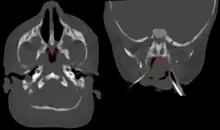

Bilateral membranous choanal atresia in CT scan

Diagnosis is confirmed using CT scan.[1][2] This is also useful for differential diagnosis.[1]